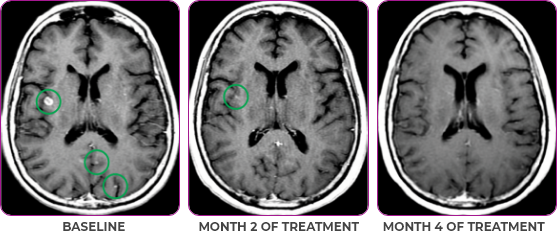

Response in primary and metastatic lesions1

MRIa imagery of the brain. Green circles indicate baseline brain metastases.1

SCAN 2: BRAIN

aMRI, magnetic resonance imaging.